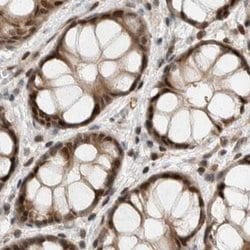

Invitrogen™ ZNF521 Polyclonal Antibody

Brand: Invitrogen™ PA554898

Immunogen sequence: VTVGYTSVSS TTPDSNLSVD SSTMVEAAPP IPKSRGRKRA AQQTPDMTGP SSKQAKVTYS CIYCNKQLFS SLAVLQIHLK TMH Highest antigen sequence identity to the following orthologs: Mouse - 99%, Rat - 99%.

The zinc finger protein 521 (ZNF521) is a transcription factor containing an N-terminal transcriptional repressor motif and 30 zinc finger domains. It plays a role in both erythroid cell and osteoblast differentiation during development, inhibiting the activities of early B-cell factor 1 (EBF1) in erythroid cells and Runx2 in osteoblast precursors. ZFP521 binds to both Runx2 and histone deacetylase 3 (HDAC3), promotes their association and antagonizes Runx2 transcriptional activity in a HDAC3-dependent manner, thereby regulating osteoblast differentiation, skeletal development, and bone homeostasis.

| Immunohistochemistry (Paraffin) | |

| Recombinant protein corresponding to Human ZNF521. Recombinant protein control fragment (Product #RP-93654). | |